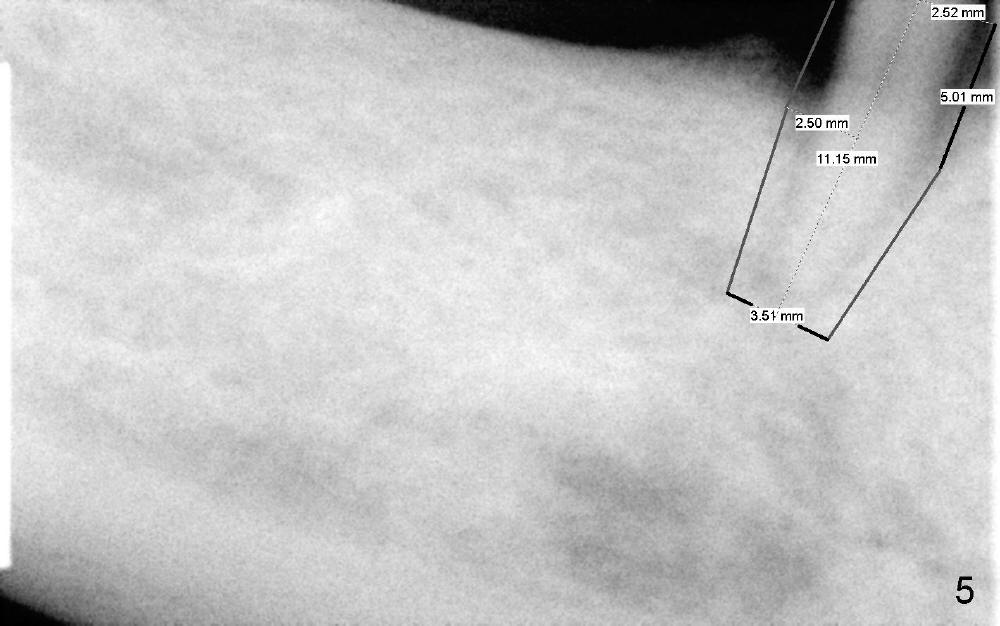

The third step to avoid paresthesia is called no drill osteotomy.  When the tooth is extracted, the depth of the socket is measured.  Tap(s) will be used to create the osteotomy (to form threads); the depth is controlled with precision.  How to decide the diameter of the implant?  It should be large enough to obtain primary stability, but an oversized implant may also injury the loop.  It is estimated that a 5x11 mm tissue-level tapered implant will be used (Fig.5) or 4.5x11 mm.  Mesiodistally the implant should be a little larger than the root, since buccolingual width of the socket is larger.  The osteotomy will be as lingual as possible, since the mental loop is buccally located.  A photo is going to be taken to show the oval shape of the socket.  If visibility is poor, a flap may be raised.